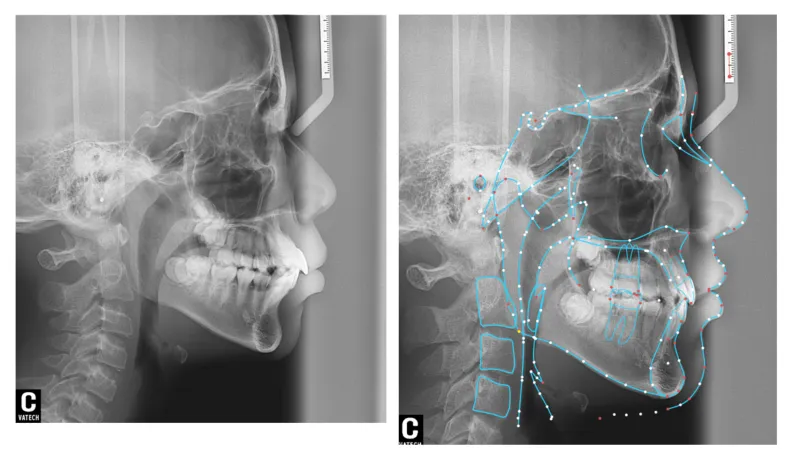

2月重点讲解辅助检查(影像、模型、拍照)的应用与解读,CBCT、口扫、模型分析等数字化工具的应用是现代正畸的核心,学员需掌握辅助检查的操作规范与结果解读能力,实现精准诊断;

病例展示: